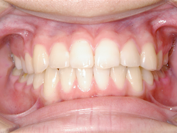

1) 主訴 前歯で咬むことができない

2) 診断名 前歯部開咬

6) 治療期間 開始時から装置装着まで3か月、マルチブラケット期間1年6か月、保定期間4年

8) 考えられる治療効果 咀嚼能力および能率の向上、構音機能の改善、口唇等の審美性の改善